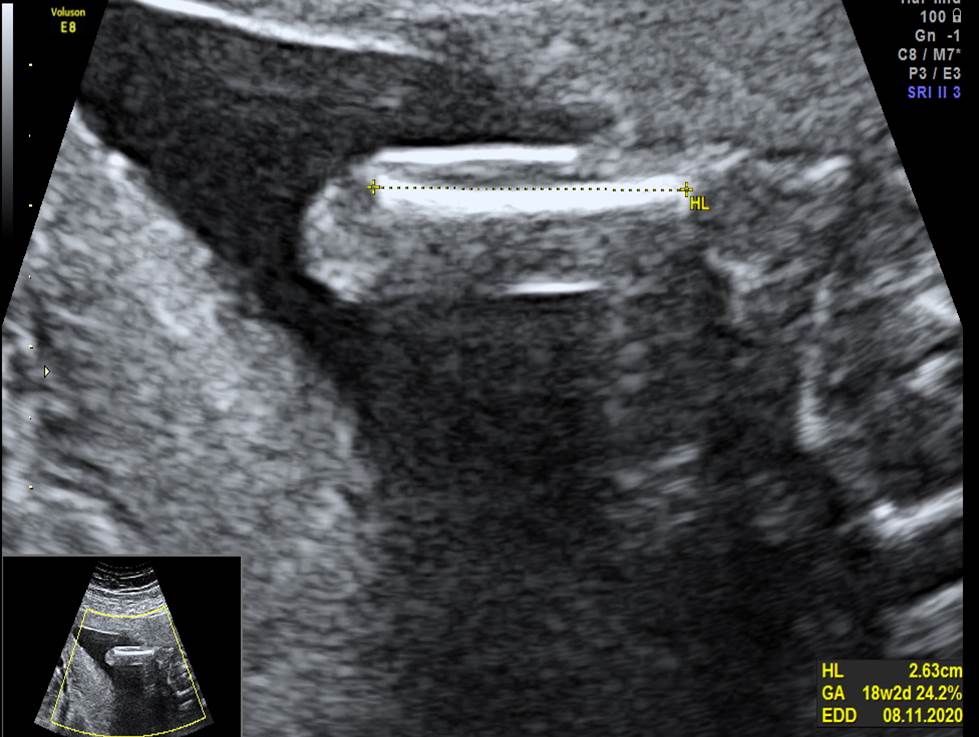

Проанализируйте изображения и видео-клипы плода в 20 недель, установите диагноз

Пациентка обратилась для получения второго мнения с диагнозом: беременность 20 недель, гипоспадия. Проанализируйте изображения и видео-клипы плода в 20 недель, установите диагноз